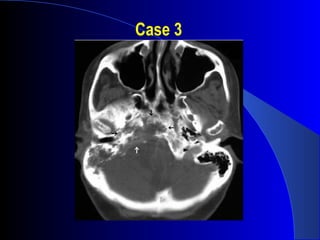

Case 1

Chondrosarcoma

CT Findings:

• Irregular, destructive mass

• Centered off midline

• Petro-occipital fissure

• Calcifications, 70%; “rings/arcs”

MRI Findings:

• Low T1 signal, high T2 signal

• Enhance with contrast

• Scalloped, well circumsribed margins

• #53 T1 post contrast MR showing extraaxial lesion arising from the middle cranial fossa. Heterogeneous enhancement. Low signal areas = flow voids or calcs. Coronal = involvement with skull base. Mass effect on temporal lobe.